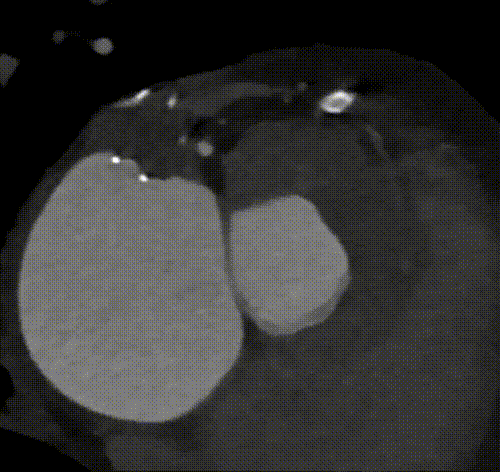

瓣环根部CTA

图1. 瓣环周长81.5mm,平均直径25.9mm。LVOT周长81.6mm,平均直径26.0mm